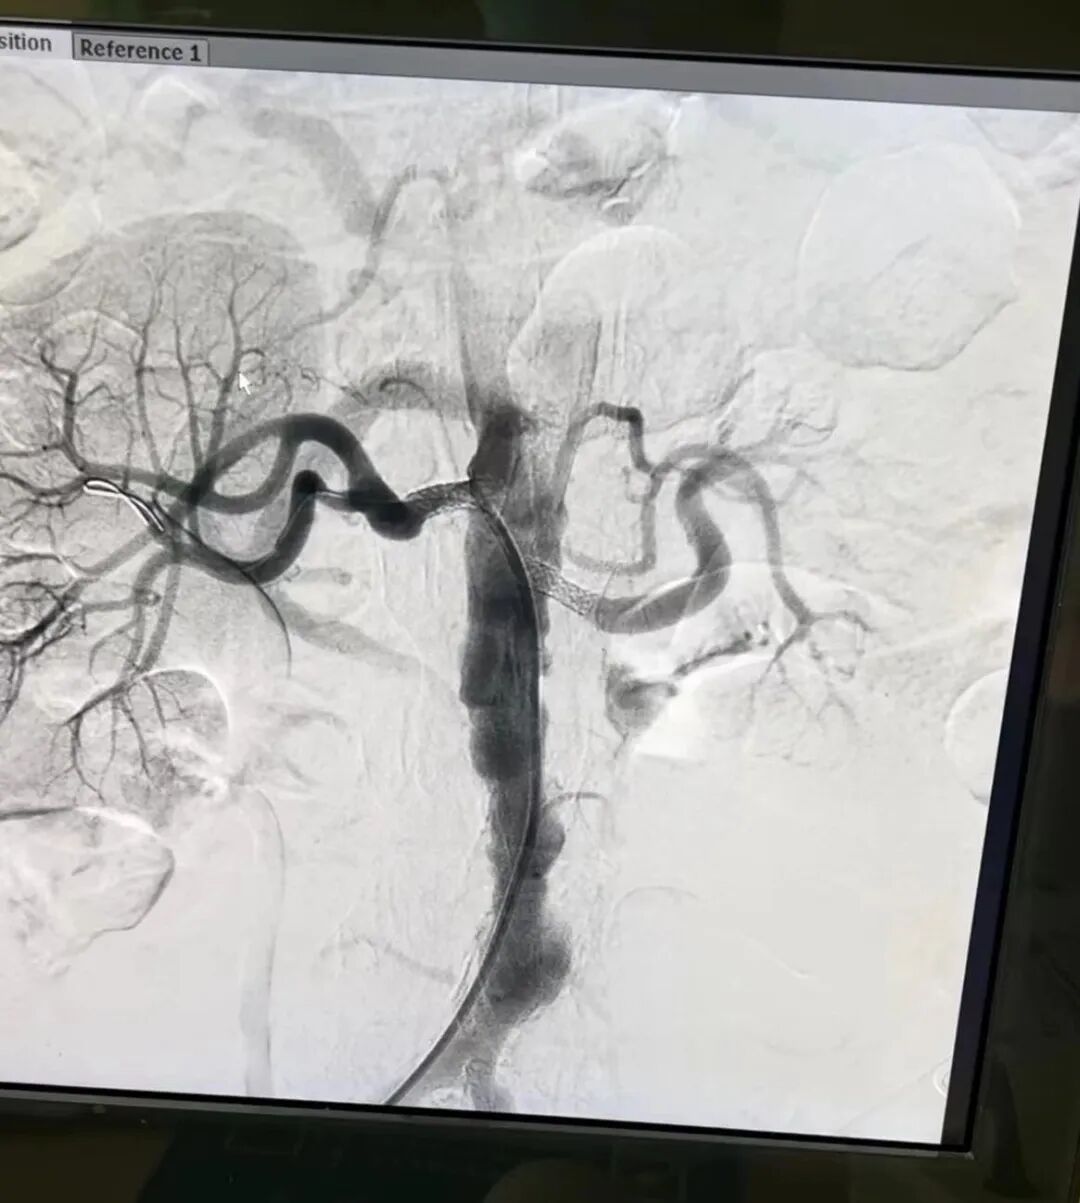

7月13日,在郑州市中心医院神经介入科专家王海波教授,介入团队副主任医师张晓平,主治医师韩旭超、邱帅兵等共同为患者行肾动脉球囊扩张成形及左肾动脉支架植入术。经过股动脉穿刺、肾动脉造影、狭窄处球囊扩张、支架植入、压迫包扎几个步骤之后,手术顺利结束。术后血压下降,头晕头痛、视物模糊等症状都得到有效改善,大大提高了生活质量。目前患者已康复出院。

神经内科一病区主任杨正伟介绍,“这个手术就像拓宽、疏通狭窄的河道一样,医生通过穿刺大腿根部的股动脉,将一个压缩得很小的球囊送到肾动脉狭窄处进行扩张,然后放血管支架,以撑开肾动脉。”